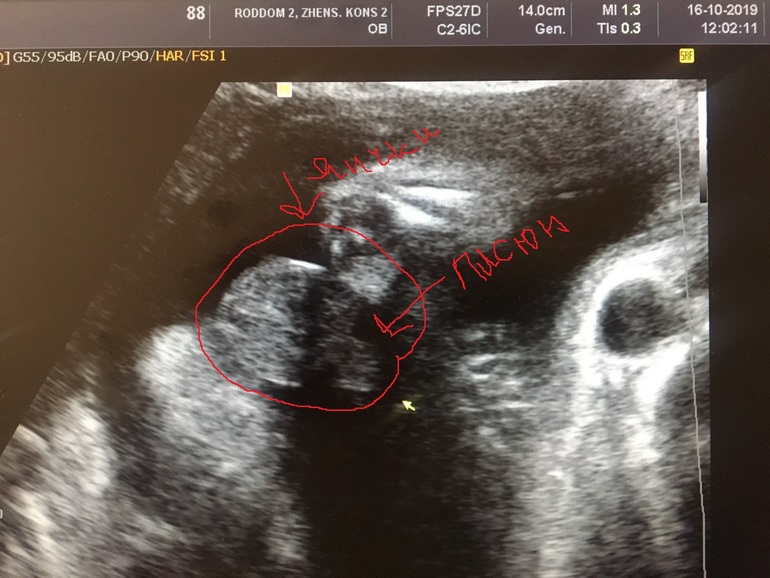

Пол малышаПошли сегодня с мужем на узи.

У нас будет мальчик😁

А шли подтвердить ДЕВОЧКУ)

Писюн на весь экран)

А где писюн то смотреть?😂

Вижу только серо-белые пятна, как там врачи понимают 🤣

Он крупным планом, ниже прикрепила фото и обвела с обозначением где он)

Да, на втором узи врач сказал, что мошонки нет, всё сглажено, ничего не торчит